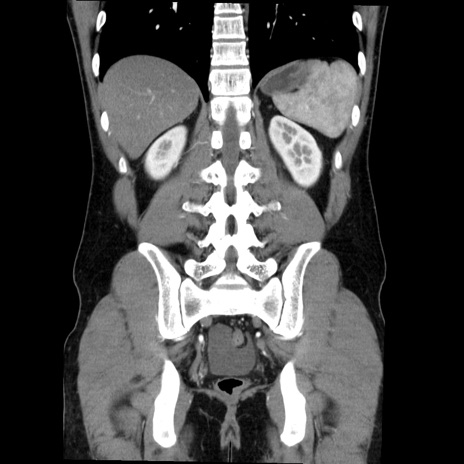

症例36(冠状断像)

【症例】20歳代 男性

【主訴】心窩部痛

【現病歴】今朝より上腹部痛あり。一旦軽快していたが再度出現したため救急要請。昨日夕に白身の魚を含む刺身を食べた。

【身体所見】BP 136/89mmHg、HR 74/min、BT 37.0℃、腹部:膨満、軟、心窩部に圧痛あり。反跳痛なし、筋性防御なし、腸雑音やや亢進あり。

【データ】WBC 17700、CRP 0.48